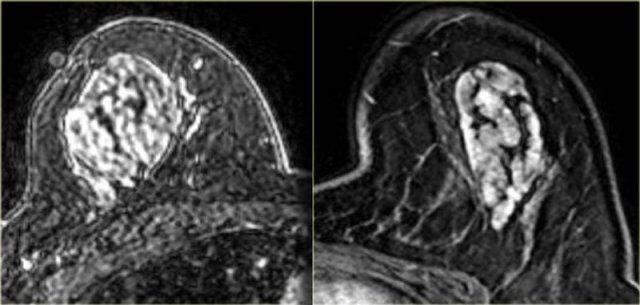

Invasive lobular carcinoma

Invasive lobular carcinoma is one of the types of cancer that does not always

show a lot of enhancement on breast MRI, which can make it difficult to diagnose.

In these two cases however, this was not a problem.

The image on the far left is of a diffuse invasive lobular carcinoma.

On the right is a MIP showing a large area of abnormal enhancement, which proved to be a diffuse invasive lobular carcinoma.